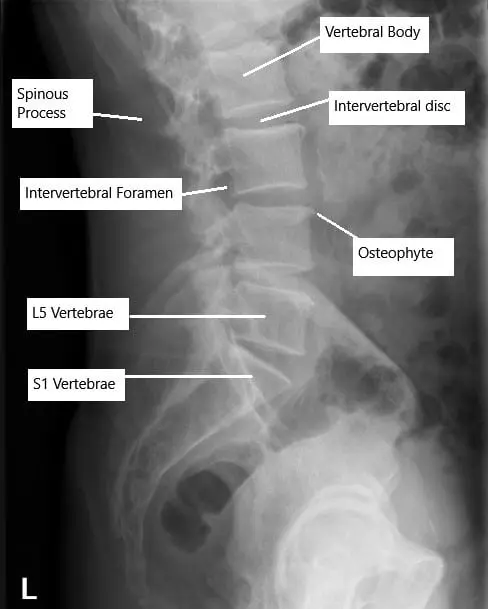

X-ray of the lumbar spine showing degenerative changes.